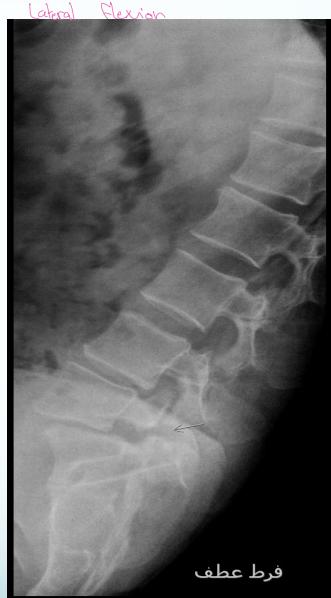

- LAT Flexion-Extension: To diagnose instability (especially in lower back pain)